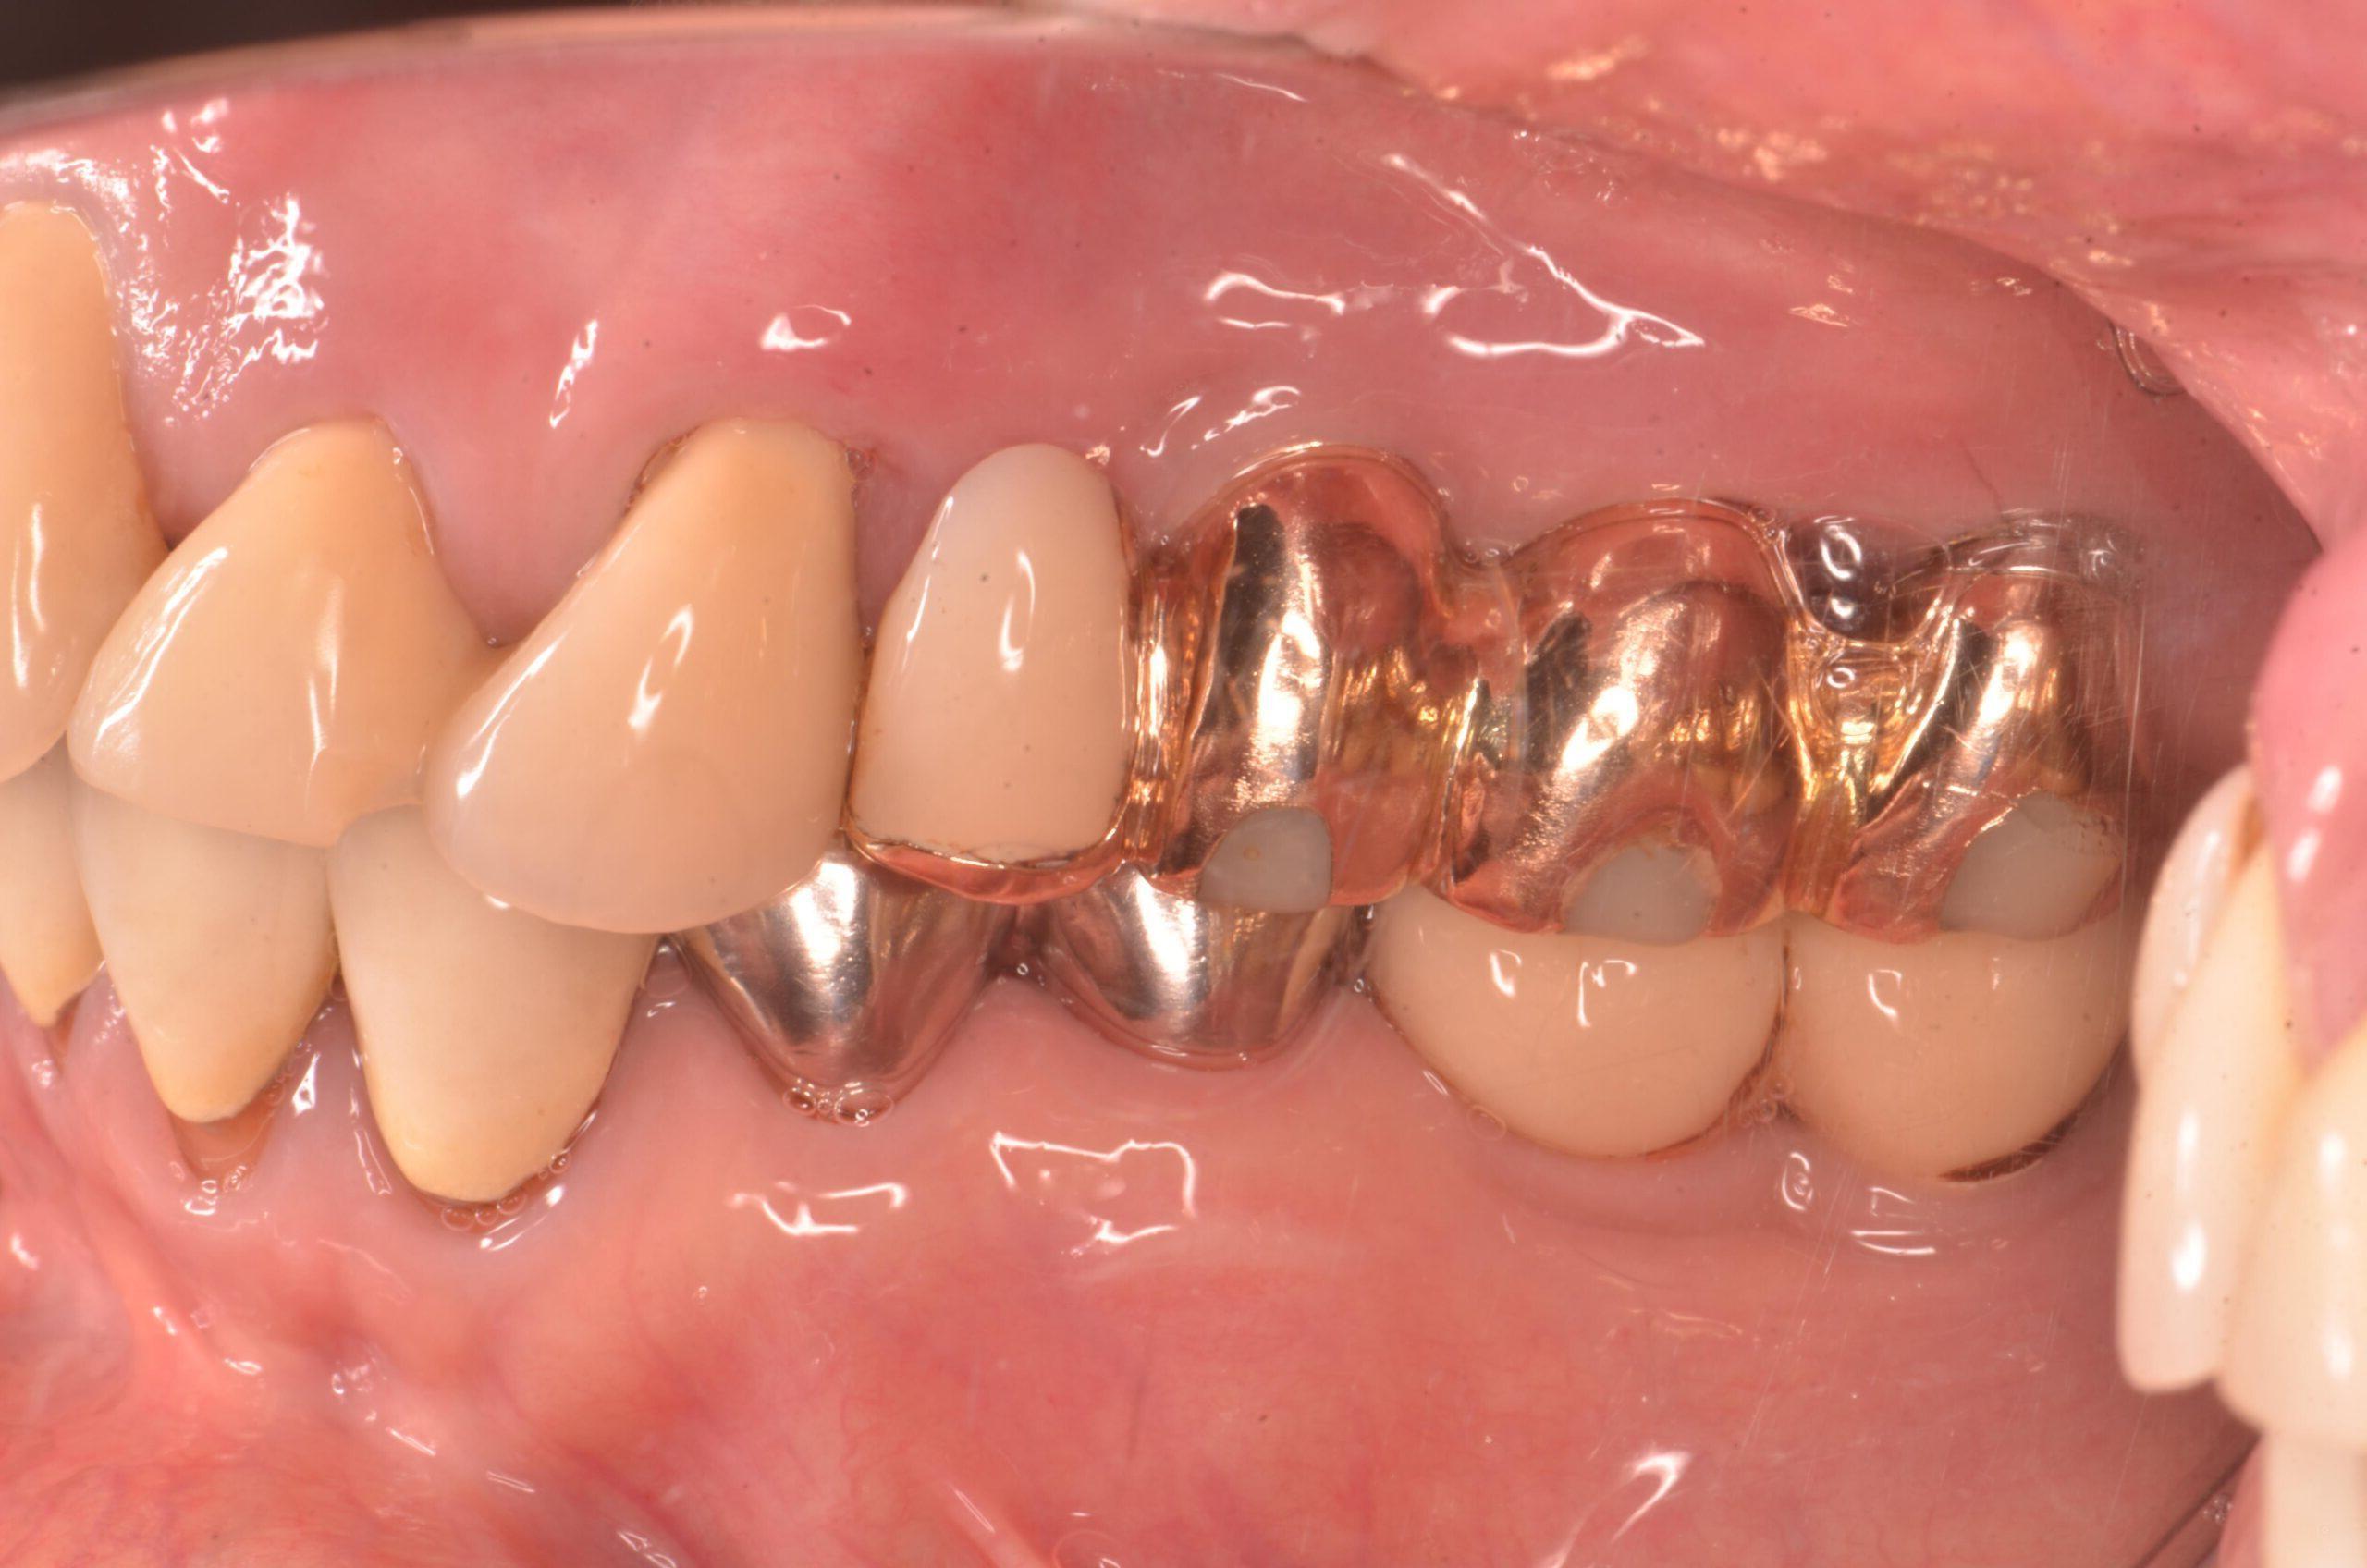

写真の症例はインプラントから膿がでています。

本症例はインプラントを消毒しても治らなかったので、インプラントのバイ菌を除去する手術で

なおさせていただき、歯ぐきはしっかりと引き締まりました。